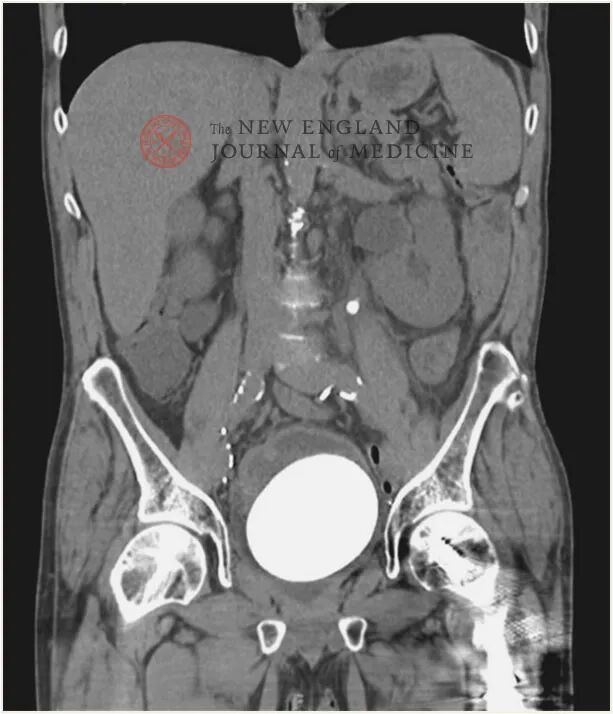

图片来源:N Engl J Med 2022; 387: 1888